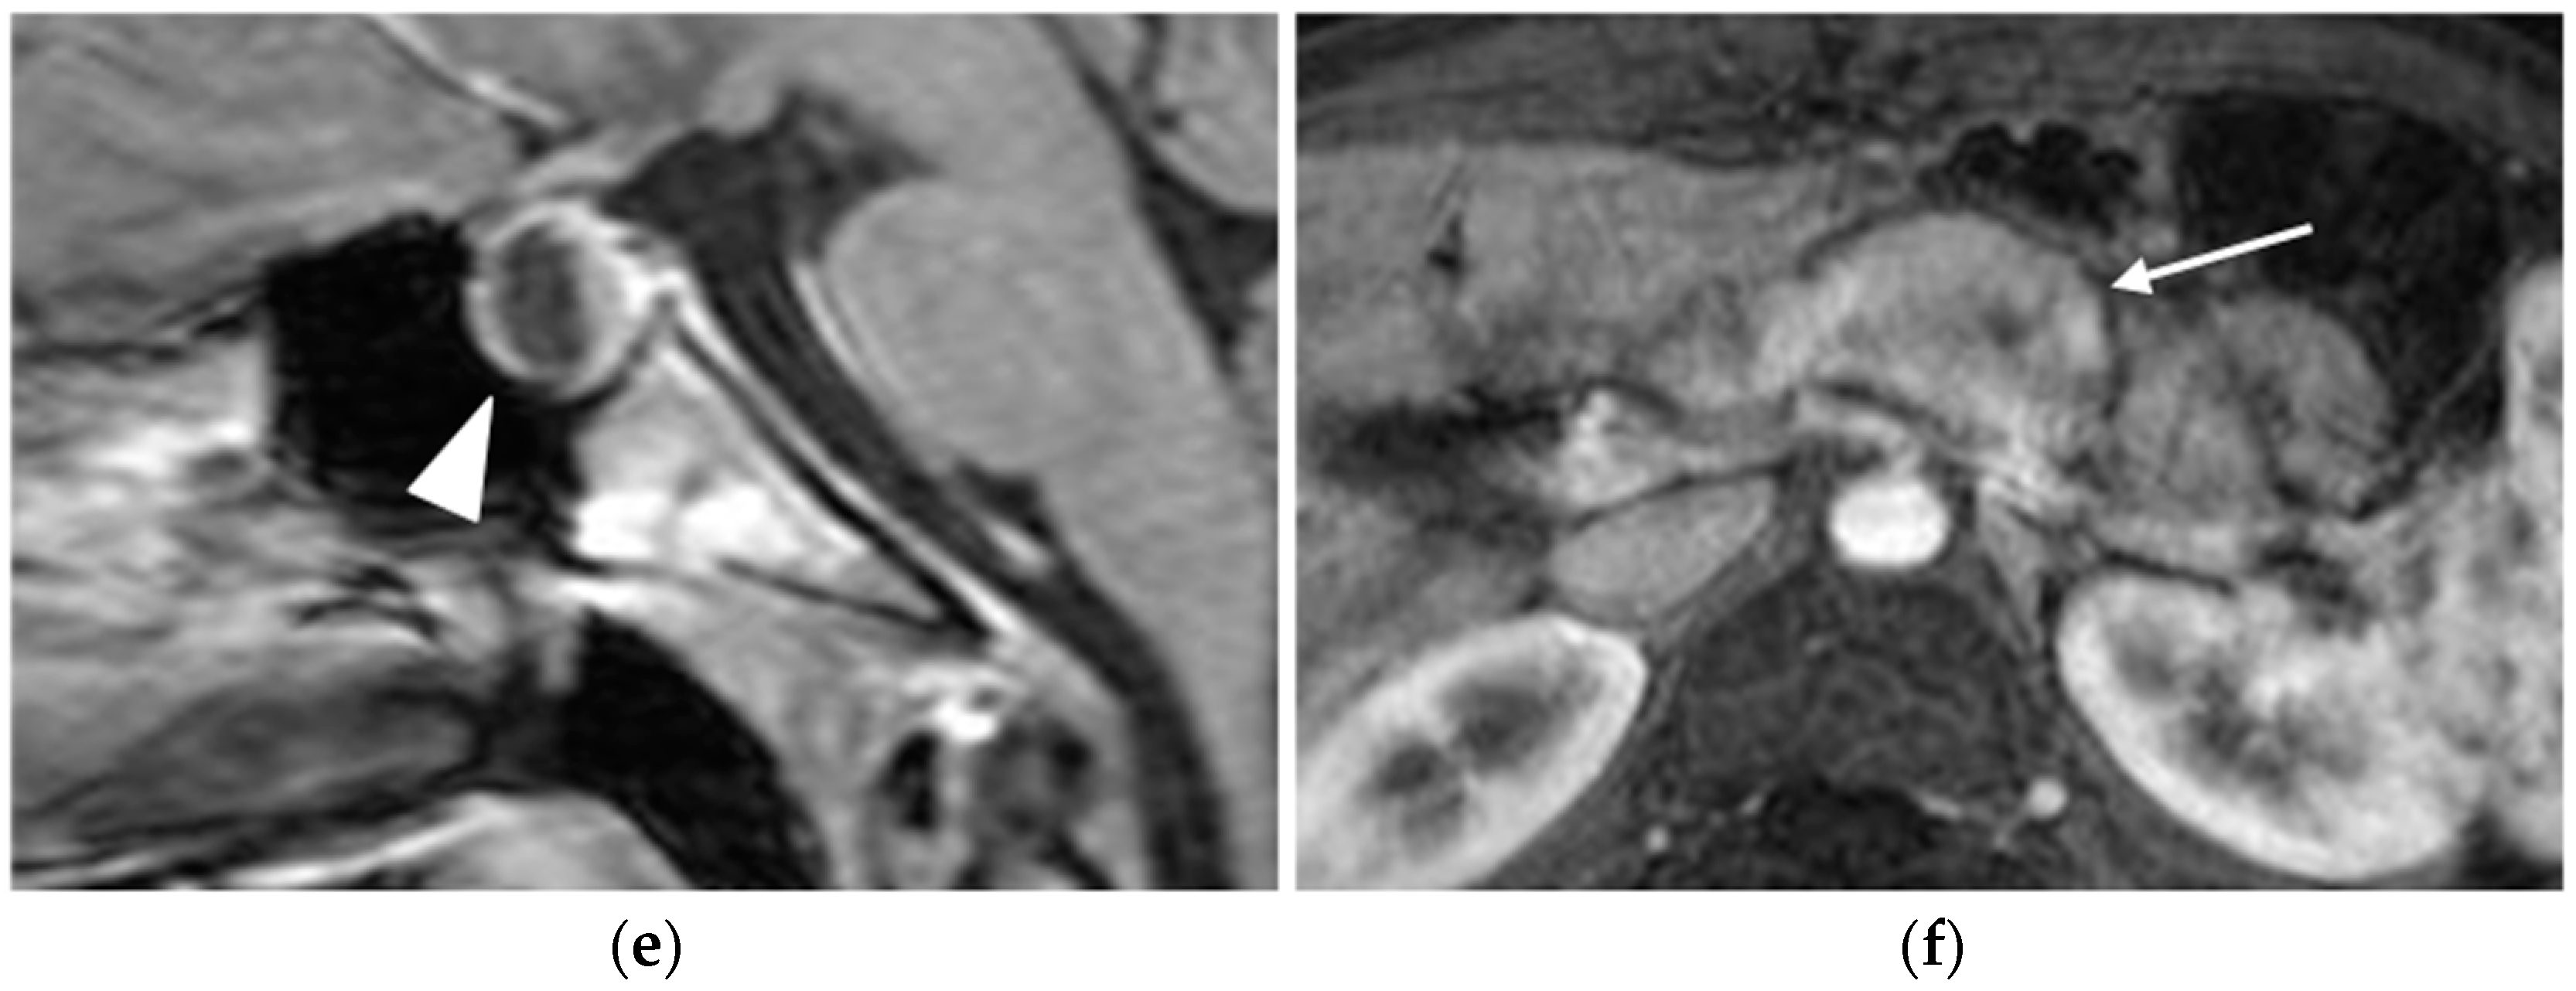

MRI

- Manfredi, R.; Bonatti, M.; Mantovani, W.; Graziani, R.; Segala, D.; Capelli, P.; Butturini, G.; Pozzi Mucelli, R. Non-hyperfunctioning neuroendocrine tumours of the pancreas: MR imaging appearance and correlation with their biological behaviour. Eur. Radiol. 2013, 23, 3029–3039. [Google Scholar] [CrossRef]

- Khanna, L.; Prasad, S.R.; Sunnapwar, A.; Kondapaneni, S.; Dasyam, A.; Tammisetti, V.S.; Salman, U.; Nazarullah, A.; Katabathina, V.S. Pancreatic Neuroendocrine Neoplasms: 2020 Update on Pathologic and Imaging Findings and Classification. Radiographics 2020, 40, 1240–1262. [Google Scholar] [CrossRef] [PubMed]